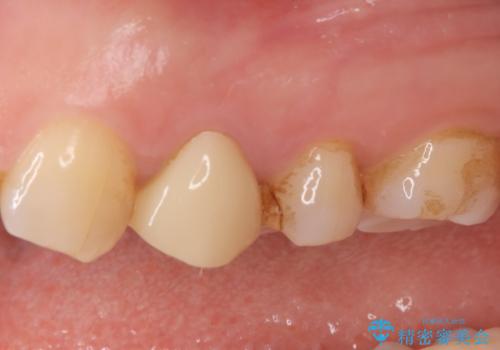

結果、根管内にはイスムスにデブリが多く見られたものの破折線は確認できませんでした。再根管治療後、症状の経過を3ヶ月ほど確認しましたが打診、違和感が消失しておらず、外科的歯内療法を行うこととなりました。

違和感という主訴に対しては、非歯原生疼痛の可能性も考慮し、専門医院への対診を優先して行うことがありますが、今回は打診が陽性だったため、患者さまの希望もあり外科を行いました。

結果、症状改善し治癒良好と判断できます。